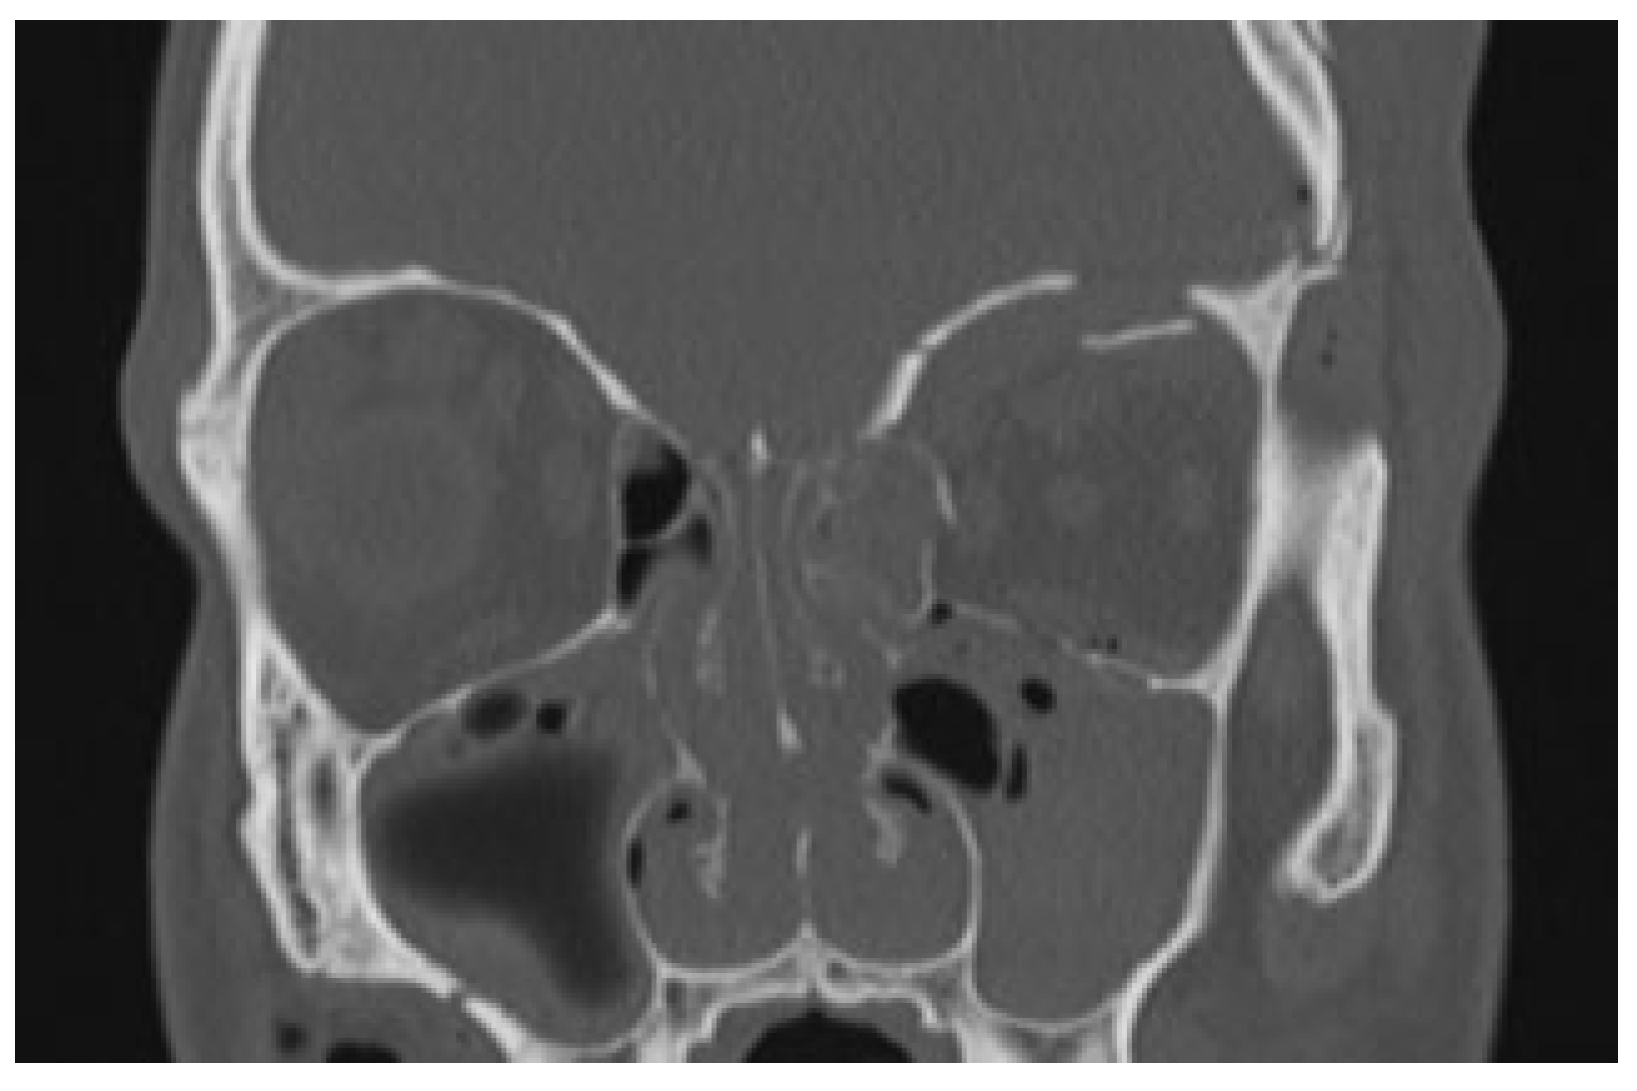

The first case is about a 22-year-old male who was involved in a high-energy trauma, scooter versus parked car. When the ambulance arrived, the patient had a maximal Glasgow coma scale despite of the fact that he had not been wearing a helmet. The patient was seen according the Advanced Trauma Life Support protocol. During the primary survey in the emergency room, there were no evident injuries to the neck, chest, abdomen, or extremities. In addition, the patient had no vision loss, no diplopia, and the sensitivity of the forehead was intact. The computed tomography (CT) showed an impression of the left frontal bone with contusion of the brain and an orbital medial wall fracture without dislocation on the left side and an orbital roof fracture on the left side with downward displacement of the fragment (

Figure 1 and

Figure 2) Despite the dislocated orbital roof fracture, it was decided to keep him under observation.